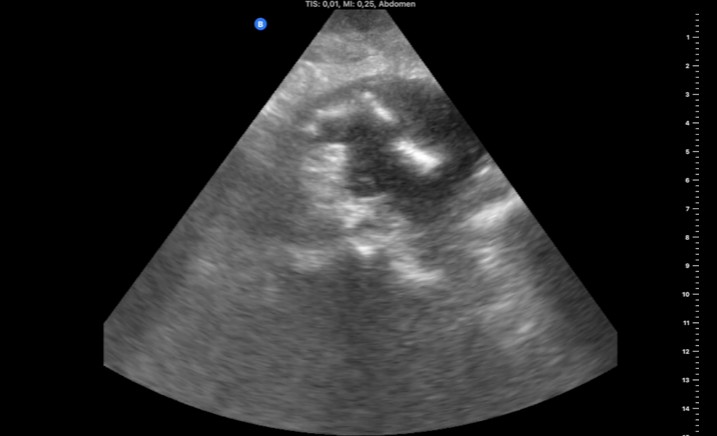

Hallazgos ecográficos

Masa ovalada de 5 x 2,6 x 4,7 cm, con pared gruesa hipoecogénica y zona central hiperecogénica (foto 1) que se prolonga por la parte craneal con el tubo digestivo (foto 2), sugestiva de neoplasia de colon.